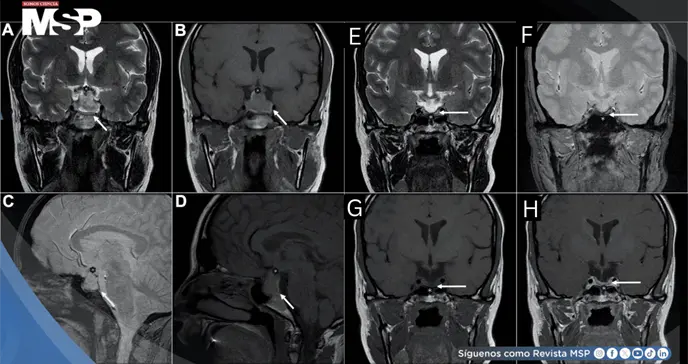

La tomografía computarizada no evidenció trombosis venosa cerebral, pero reveló agrandamiento del macroadenoma con componentes hiperatenuantes sugestivos de hemorragia, consistente con apoplejía hipofisaria.

La resonancia magnética confirmó el diagnóstico, demostrando crecimiento tumoral a 23×25×13.5 mm con extensión supraselar, desplazamiento del quiasma óptico y productos hemorrágicos agudos.